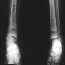

RADIOGRAPHIC EVALUATION: Osteopenia, subcortical resorption, lucent metaphyseal bands, widening of metaphysis and "rugger jersey spine".

RADIOGRAPHIC:

Early - Osteopenia

Thinning of cortices and trabeculae gives "ground glass" x-ray

Salt and pepper skull

Physeal thickening and fraying of metaphysis, no cupping

Late epiphyseal ossification

Epiphyseal Slips - Preschool age: Proximal and distal femoral and distal tibial

Older Children: Proximal femoral and distal forearm

Late - Secondary hyperparathyroidism

Subperiosteal cortical resorption - Distal phalanx, end of clavicle, ischium, pubis, SI joints, metaphyseal-diaphyseal junction of long bones

Lucent metaphyseal bands - Growth zone changes are the best indicator of severity of secondary hyperparathyroidism

Bowing of long bones

Rugger Jersey spine - Osteosclerosis of the end plates of the vertebral bodies

Brown Tumor (rare) - Rib or jaw

Amyloidosis - Multiple bone cysts: Metacarpals, hip, wrist, prox humerus, pubic rami and proximal tibia.